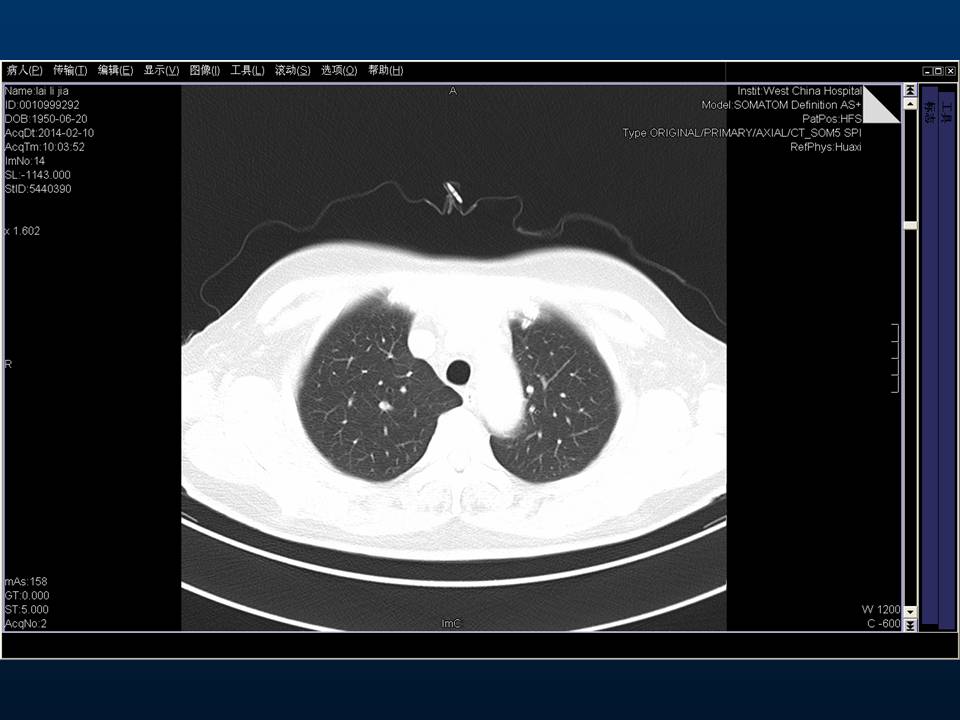

心房颤动(扑动)与“心衰”一例特殊病例报道